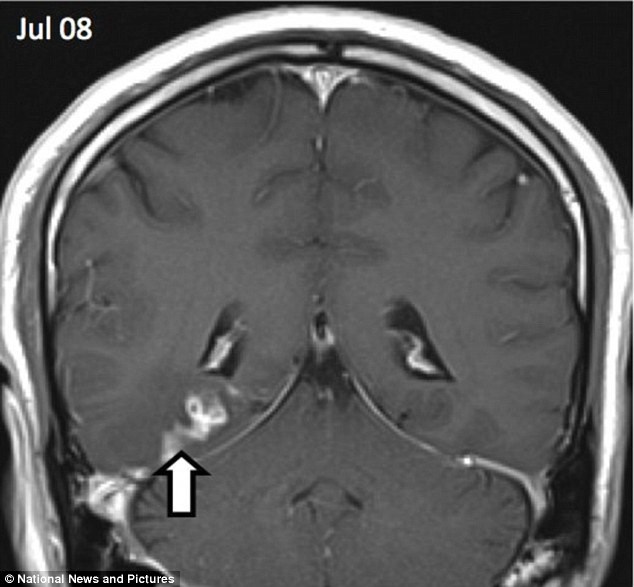

Hình chụp X-quang của một người đàn ông cho thấy anh ta đã bị một con sán dây dài 1cm đào sâu tới 5cm vào não từ trái qua phải.

Con sán dài 1cm đã đào sâu tới 5cm vào não bệnh nhân (ngày 8/7)